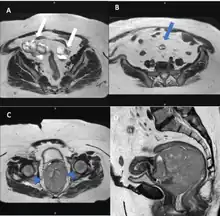

Pelvic MRI images. A: Axial T2-weighted image shows multicystic neoplastic masses (white arrows) with solid components in both ovaries. B: A peritoneal implant (blue arrow) with similar characteristics to the ovarian lesions is seen in the peritoneal cavity. C and D: T2-weighted images of the uterine cervix in the axial and sagittal plane reveal the bulky cervical tumor. The cervical stromal ring is well preserved (arrowhead)[18]

Although magnetic resonance (MRI) scans are not commonly employed for ovarian cancer detection, the majority of ultrasound-detected ovarian masses are usually benign. The combined approach of ultrasound with Doppler, along with the selective use of contrast-enhanced MRI, proves to be an efficient diagnostic method for identifying benign adnexal masses with distinctive features, including functional masses, dermoid, endometrioma, fibroma, pedunculated fibroid, hydrosalpinx, and peritoneal inclusion cysts.[19] This integrated diagnostic strategy is effective in preventing unnecessary surgical intervention. Additionally, the use of MRI contributes to a decrease in false-positive diagnoses, ultimately reducing the overall number of unnecessary surgical procedures related to ovarian masses.